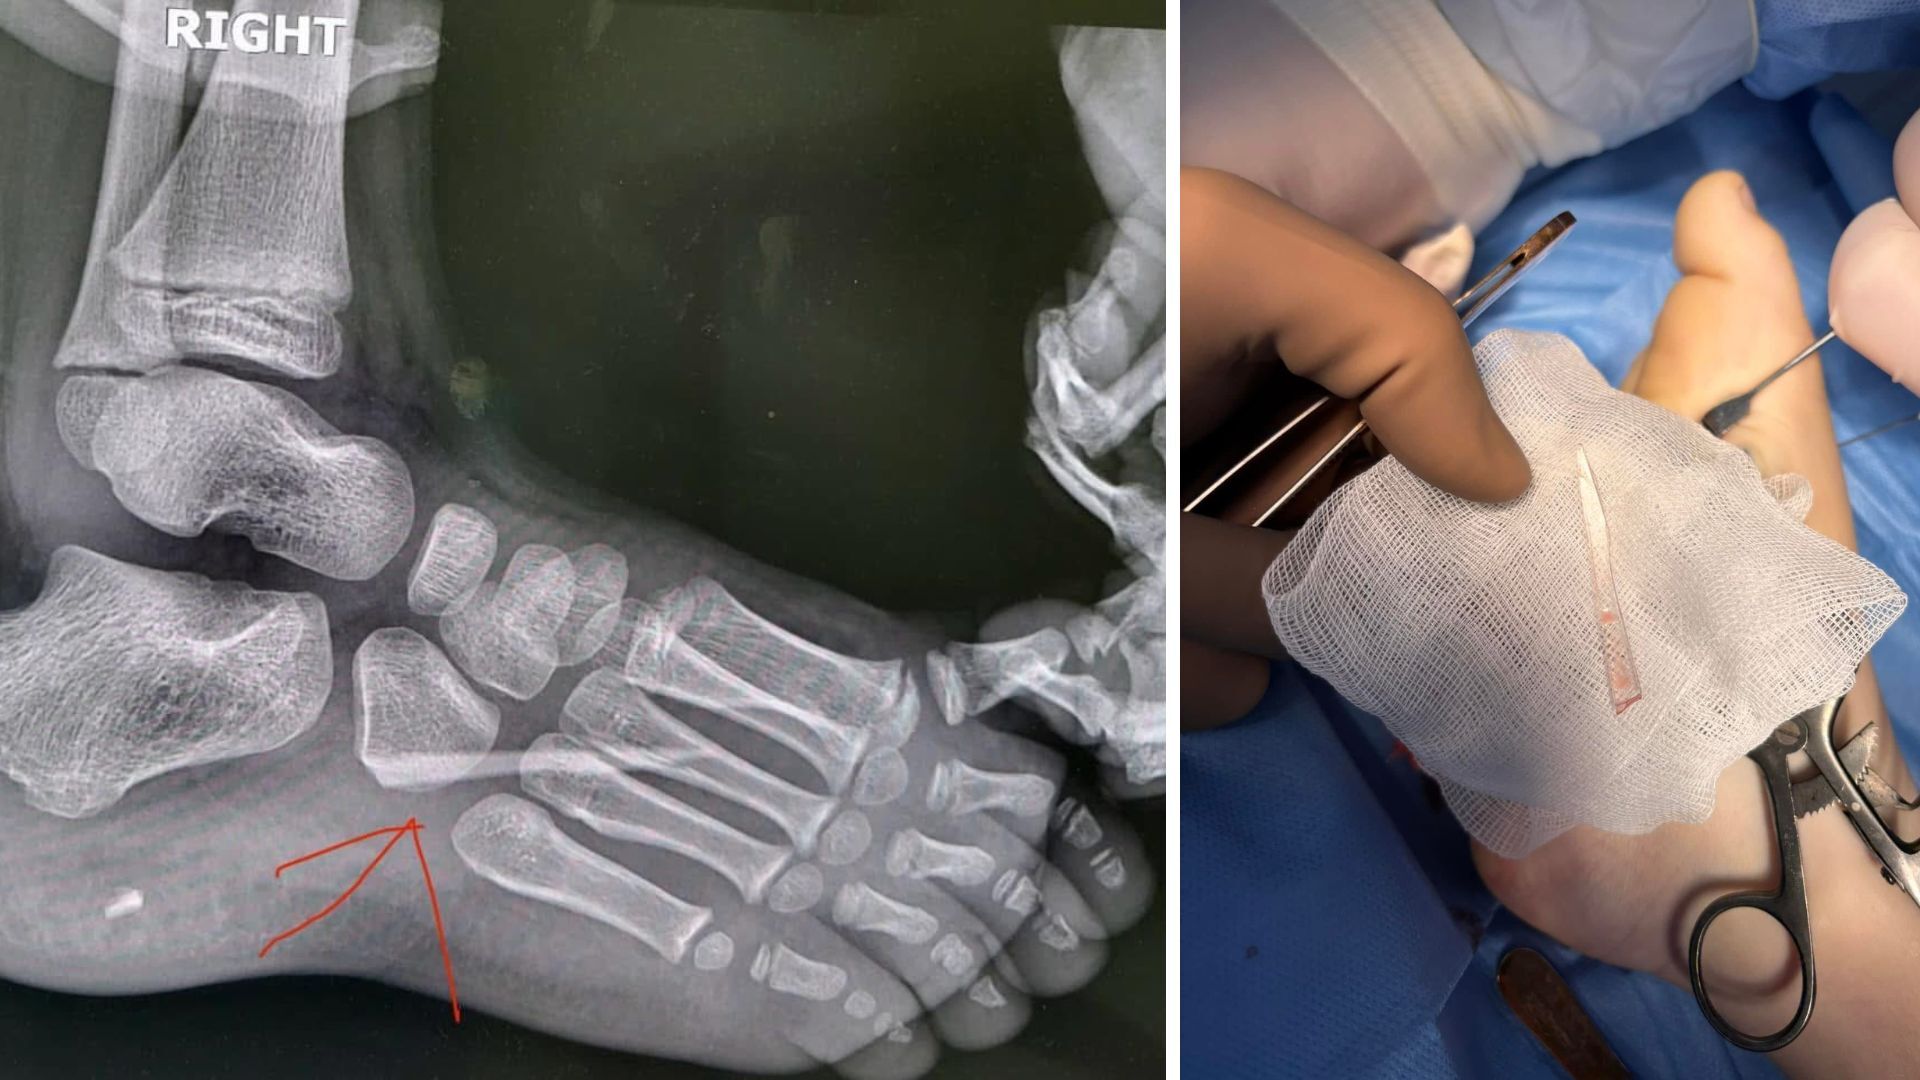

Дитина не скаржилася на біль, тому батьки запідозрили проблему лише після зміни ходи. Рентген виявив у стопі великий уламок скла.

Після клінічного огляду та рентгенологічного обстеження лікарі виявили у стопі стороннє тіло — великий уламок скла. Медикам вдалося успішно провести операцію та видалити уламок без ускладнень.